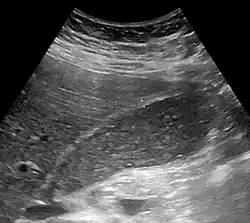

| Abdominal ultrasonography showing biliary sludge and gallstones | |

Biliary sludge is typically diagnosed by CT scan or transabdominal ultrasonography.[1][2] Endoscopic ultrasonography is another more sensitive option. However, the gold standard is considered to be direct microscopy of aspirated gallbladder bile.[1][2] This method is much more sensitive, although it is less practical.[2]